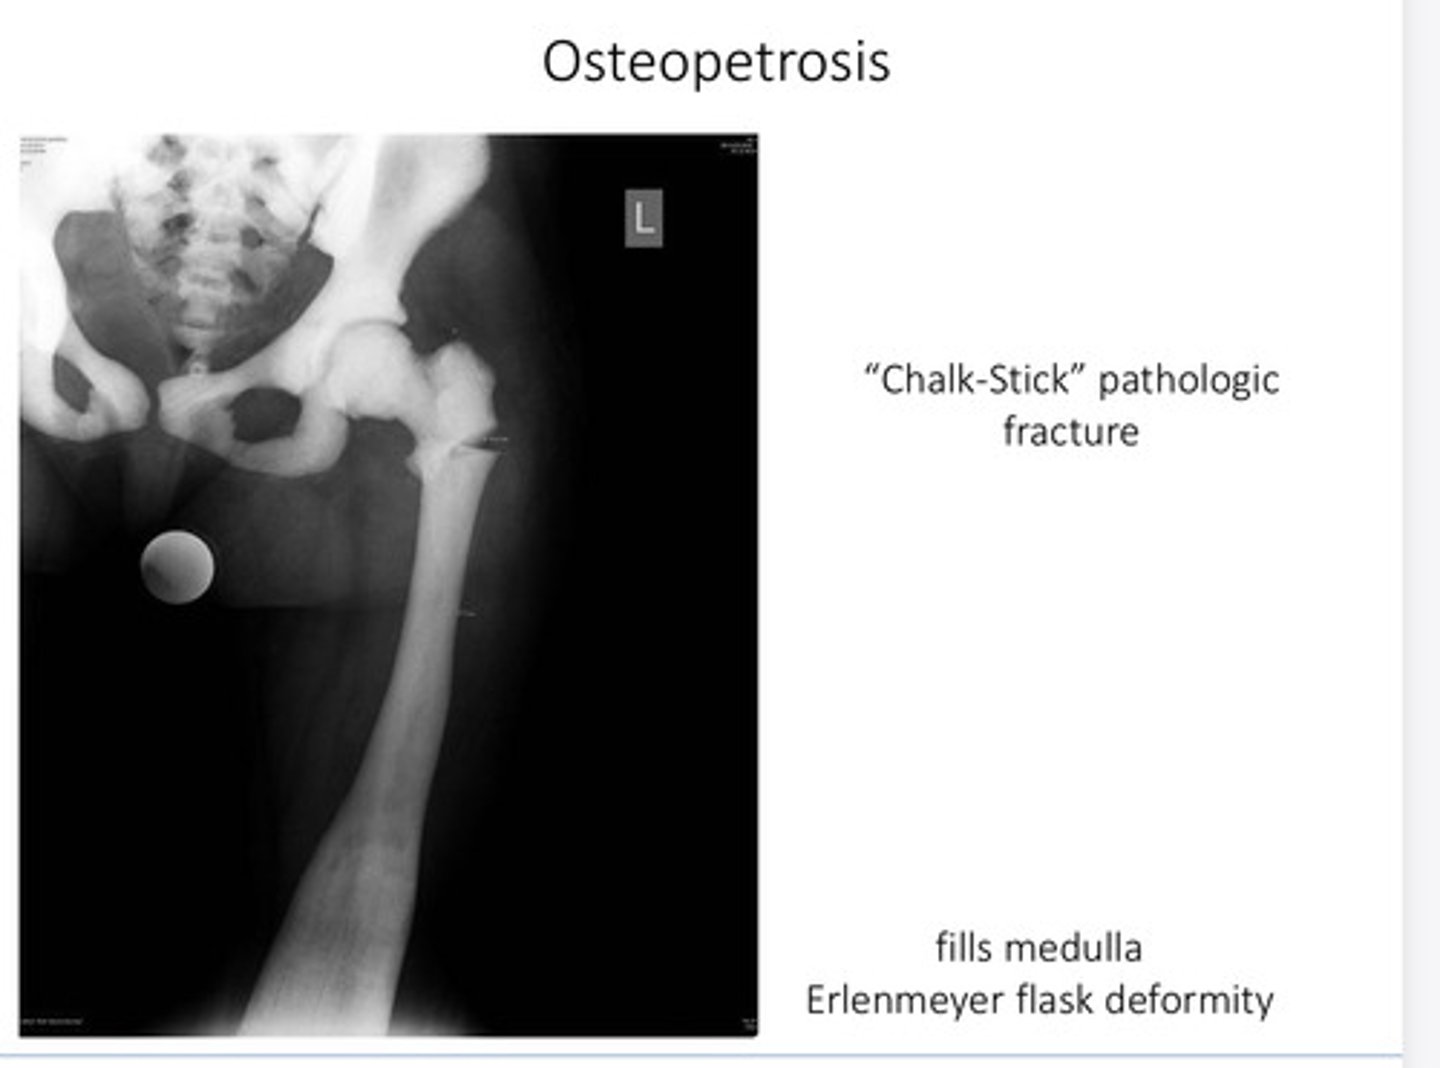

What is another name for osteopetrosis?

"marble bone disease"

What is osteopetrosis?

• Skeletal sclerosis (↑ density of bone)

• fractures: brittle

• Bony stenosis = cranial nerve palsies

• Deranged hematopoiesis

• fatigue & infections

What is a chalk stick pathological fracture associated with?

Osteopetrosis

What is an Erlenmeyer flask deformity associated with?

What is the root of the problem of Osteopetrosis?

- ↓ osteoclast activity

- loss of hematopoietic bone marrow

- ↓ Ca++ intake and/or stem cell transplant

What can a decrease in osteoclast activity?

- impaired acid production in osteoclasts

- Inability to remodel & resorb bone

- Leads to dense & thick, but brittle bone